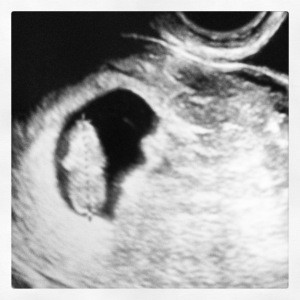

I immediately emailed my doctor to set up our 1st appointment, and we were able to see baby & hear baby’s heartbeat for the first time on January 14th – it was 152 beats per minute.

Baby K's 1st Ultrasound

Baby K’s 1st Ultrasound